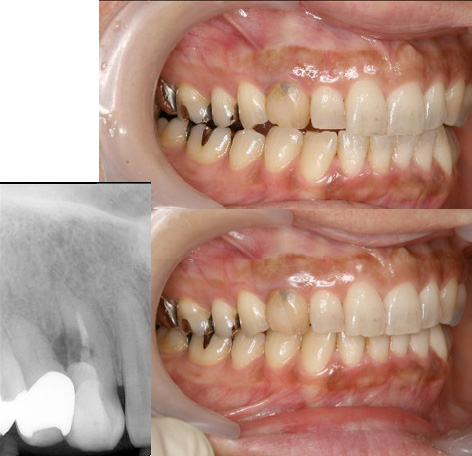

んです。右上の写真はスタッフが何気なく「歯を合わせてください」と言って撮った写真です。記録

としては下のように奥歯が噛み合った写真を撮るんですが、筋肉が楽

な位置(無意識に合わせた位置)は噛み合ってません。無理に噛もう

とすると、下の写真のように下顎をもっと後ろに持って行かないとい

けないんです。虫歯じゃないのに歯が痛くなって、神経を取った経験

のある方も多いでしょう。噛み合わせ位置が悪いと余計な力が歯に加

わり、痛みが出たり、歯が欠けたり、ヒビが入ったりしま

す。その結果、神経を取ったり、抜歯になります。